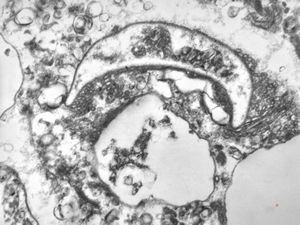

F,65y. | Epstein-Barr virus - hairy leukoplakia of tongue